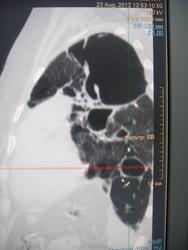

Больная с 03 года выявлена с диагнозом ФКТЛ. Ведет асоциальный о  браз жизни, лечится по настроению. На снимках- одни страсти и таких живучих больных- хроников уже мало. Абацилирована с 06года, если бы высевала, ведя такой образ жизни, давно бы сгинула.

Впечатляет...

Да, по всей видимости, на обычных рентгенограммах, возможно и томограммах, картинка весьма напоминает фиброзно-кавернозный туберкулёз, который, как трактует фтизиатрия относится к запущенным формам туберкулёза, за который ох как сильно бьют!

Не могу сказать, что видел сильно много ФКТ, но видел..., а представленный случай, на мой взгляд ФКТ не "пахнет". При таких то полостищах, а может быть и кистах слева, довольно интеллигентная картинка справа...

А может быть то не бывшие "каверкоты", а дизонтогенетические кисты?

особенности патологической анатомии туберкулеза, сочетающегося с кистозной гипоплазией легких был изучен выдающимся русским патологоанатомом, антропологом, биологом В.Г.Штефко. 100-летие В.Г.Штефко было отмечено в 1993 году.  В.Г. Штефко считал, что  дегенеративные легкие особенно восприимчивы к туберкулезной инфекции. Мнение В.Л. Катенёва ("а дизонтогенетические кисты?") не фантастика. Вероятность того, что туберкулез легких развился на фоне порочного легкого, очень даже высока. Кроме того, отечественными исследователями подробно описано "разрушенное легкое", как исход прогрессирущих форм туберкулеза.